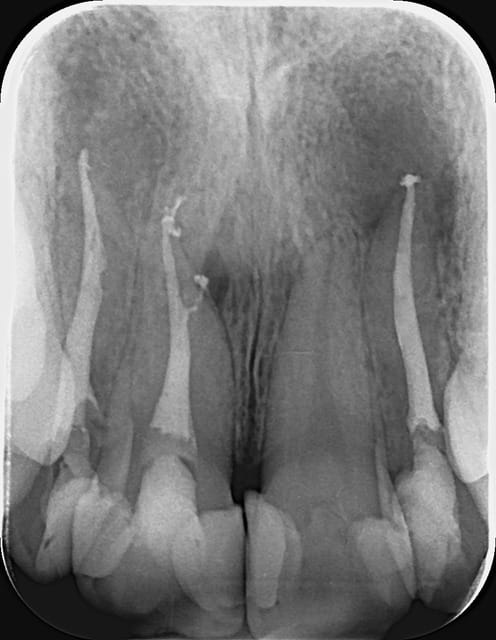

> 11,22 - test de vitalité - négatif

> - percussion - peu positif

>

> premier visite 2,5 heures

> - isolement digue

> - instrumentation manuel 11 - 55/0.10; 22 - 40/0.10

> - irrigants active par ultrasons NaOCl 5% ; citric acid

> 5 jours avec hydroxyde de calcium

> deuxième visite 1,5 heures

> - obturation endodontique - 2/3 condensation laterale a froid; apres chaud

> verticale condensation pour assure l'étanchéité 1/3 apicale

> Indication - radiografie de contrôle apres 3 moins